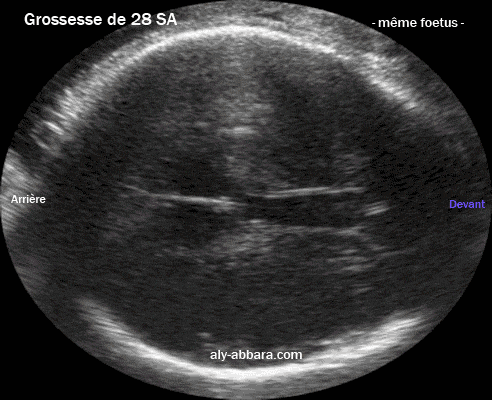

Coupe transversale puis sagittale médiane du cerveau fœtal à 28 SA |

| Sur la coupe transversale, en

passant par le cavum septum lucidum et le cavum vergae l'observateur peut avoir l'impression de l'existence d'un élargissement du septum lucidum. Sur la coupe sagittale médiane, en traversant le corps calleux on observe qu'il s'agit d'un cavum septum lucidum normal et d'un cavum vergae également normal. |